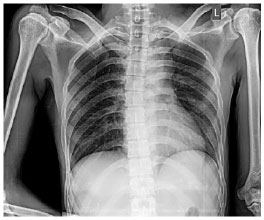

His blood laboratory test results presented low hemoglobin, lymphocyte, erythrocyte, hematocrit, creatinine, and sodium levels; however, high basophil count, neutrophil segment, monocyte levels, and neutrophil-lymphocyte ratio have been observed. The patient got packed red cell (PRC) transfusions. Head computed tomography (CT) scan showed left side hypodense lesion in the fronto-temporo-parieto-occipital region and vasogenic edema (Fig. 1). Thorax imaging showed no abnormalities (Fig. 2).